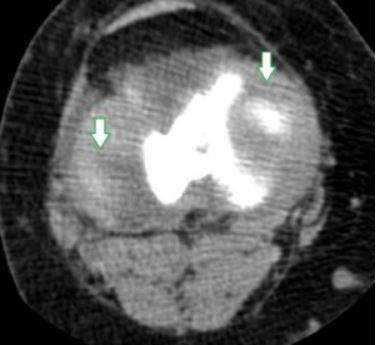

КТ мягких тканей колена: стрелки указывают на места, где расположены нечетко видимые мениски

МРТ мягких тканей коленного сустава: 1 и 2 - мениски латеральный, медиальный, 3 - межменисковая связка